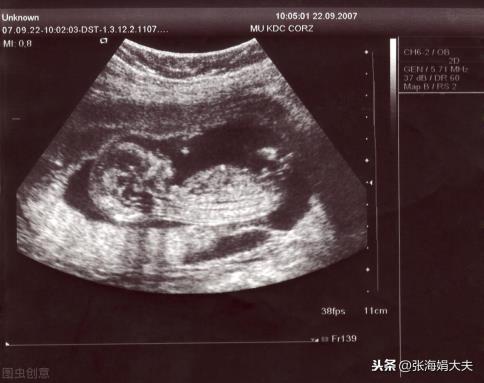

起初一次偶尔的机会看见了1个我的文章,也是一位患者都筹备去做试管了,结果经过调节就自然的怀上了,夫妻俩决议抱着试试看的心态搜到了我,心想万一就能怀上了呢?经过广泛的检验以后我发掘,肌体并没有什么大的问题,首要是因为吴女士子宫内膜太薄了,这才造成就算是做了试管也没有顺利的原因。内膜场景不好,就相当于种庄稼的地皮不好,没有方法扎根下去,因此自然就没方法怀上宝贝了!经过评价以后我决议祖先工的“毁坏”内膜,督促内膜的自我修复本领,与此同时对于性用药调节,督促内膜的生长,就如此调节了3个周期,内膜增长较好根本上满足了怀胎的需要。由于夫妻两边的J子还有卵子全是没有问题的,因此所有全是水到渠成,在引导下安排排卵期同房,当月试孕当月顺遂怀上宝贝。

如今怀孕已然有3个月的时间了,孕检优良宝贝发育所有常态,祝贺她们如愿的具有了自身的宝贝,高兴高兴!期望大家也都能这样好孕~